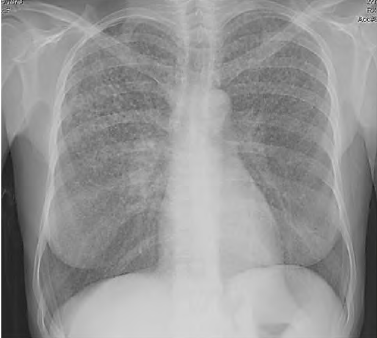

Uma paciente de 45 anos de idade compareceu, acompanhada pela filha, a uma consulta ambulatorial. Queixa-se de perda de peso (em torno de 4 kg nos últimos seis meses), febre vespertina e fadiga há mais de 20 dias. Observe que tem trabalhado muito, tem uma fadiga crônica e acha que iniciado os sintomas após exposição à chuva e o frio quando voltava do trabalho para casa. Ela informa que é etilista social e tabagista (15 cigarros / dia), e alguns exames laboratoriais como hemograma, eletrólitos, função hepática e renais normais. Os raios X de tórax estão representados na imagem a seguir. O resultado do PPD e o lavado brônquico são negativos.

Com base nesse caso clínico, na imagem apresentada e nos conhecimentos médicos correlatos, julgue o item a seguir.

Os hábitos de vida dessa paciente podem estar relacionados à queixa de fadiga crônica.